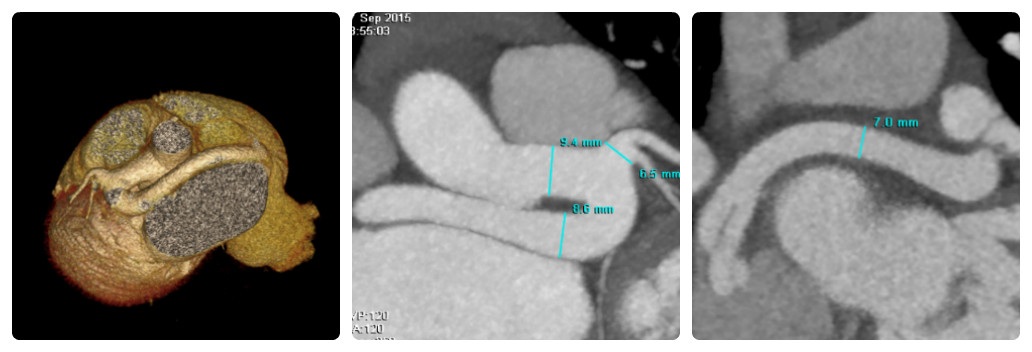

Мальчик Е. 11 лет 29 кг, поступил в клинику с диагнозом коронарно-предсердная фистула с жалобы на одышку при физической нагрузке, быструю утомляемость. По данным рентгенографии грудной клетки СЛК 65%. Трансторакальное ЭХО КГ показало расширение устья и ствола левой коронарной артерии до 1 см, а также турбулентный поток в правом предсердии, по цветной доплерографии размер потока 4,8 мм, повышено расчетное давление в ЛА 48 торр. На МСКТ исследовании с контрастом, подтверждена коронаро-правопредсердная фистула. Диффузно расширенный сосуд 10,5х8,5 мм, отходил от левого синуса Вальсальвы, который имел U-образный изгиб от которого отходили Cx и LAD. Ретроаортально между восходящей аортой и левым предсердием расширенный сосуд дренировался в полость правого предсердия в виде двух теснорасположенных стволов диаметрами 7 мм и 6 мм.

Для дальнейшего исследования пациент направлен на катетеризацию сердца. Исследование выполнено на спонтанном дыхании, без кислорода. Сосудистый доступ осуществлялся через правую бедренную вену и левую бедренную артерию. Использовались диагностические катетеры 4 Fr Terumo. Контрастирована коронаро-правопредсердная фистула, выявлено максимальное расширение до 13 мм. При выполнении селективной коронарографии стенозирующей патологии коронарных артерий не выявлено. Определяется нормальная анатомия венозного возврата в истинный корорнарный синус, который расположен в правом предсердии. Давление в ПП 14/8(11) торр, в ПЖ 50/3(23) торр. Произведены заборы крови из камер сердца и магистральных сосудов на оксигинацию - Qp/Qs 1.6. (рис. 1).

Рис. 1: МСКТ коронаро-правопредсердной фистулы: А) трехмерная реконструкция КФ, краниальная проекция; B) контрастное МСКТ, прямая проекция, отношение фистулы и ЛКА; С) прямая проекция, показано место дренирования КФ двумя раздельными стволами в правое предсердие.